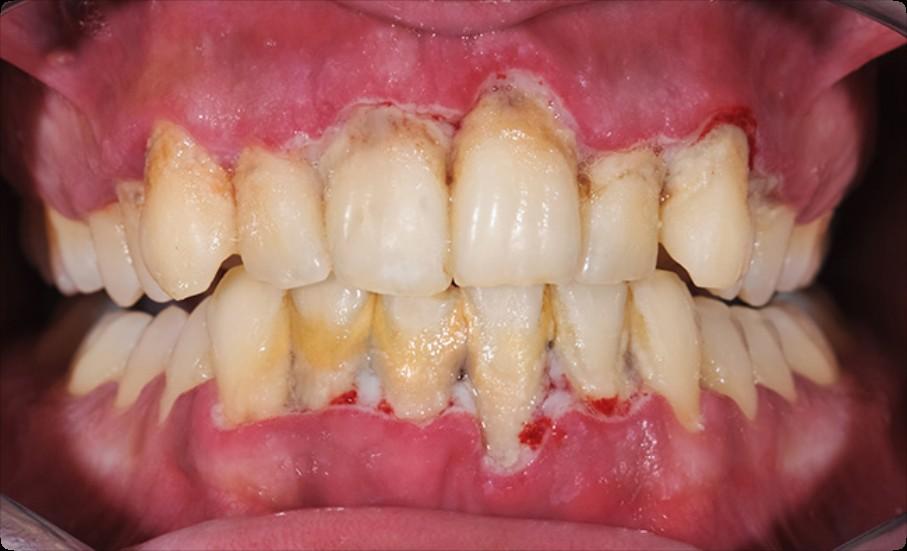

Beyond Myeloma Therapy: Oral Health Survivorship

Katharine (Kate) Ciarrocca, DMD, MSEd

Director, Oral Medicine, Duke University Hospital

Common Complications of Cancer Therapy

Why is the mouth so susceptible?

Oral Health During Cancer Treatment

Treatment Related Oral Complications

Due to both direct damage to oral tissues secondary to cancer treatment and indirect damage due to regional or systemic toxicity

The Role of Basic Oral Care (BOC)

• Reduces the risk and severity of oral complications.

• Improves the likelihood that the patient will successfully complete planned cancer treatment.

• Prevents, eliminates, or reduces oral pain.

• Minimizes oral infections that could lead to potentially serious systemic infections.

• Prevents or minimizes complications that compromise nutrition.

• Improves the quality of life.